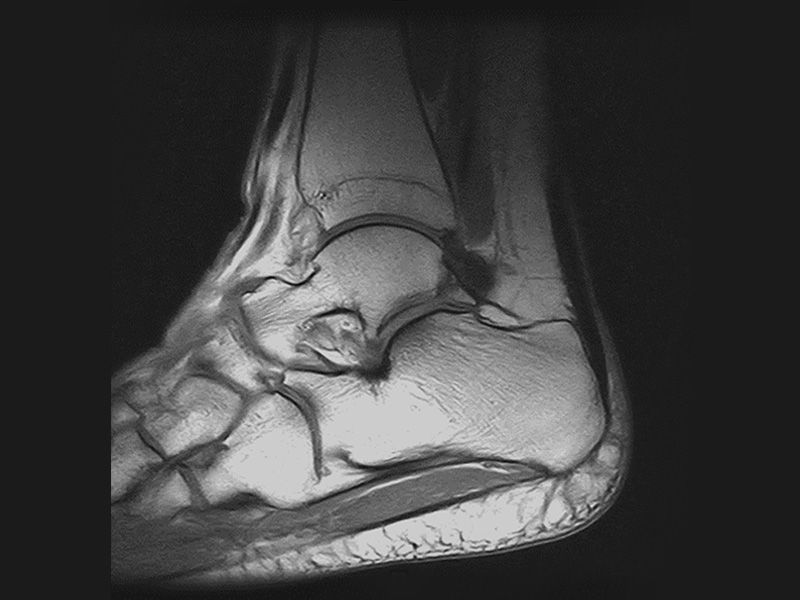

Klinické snímky